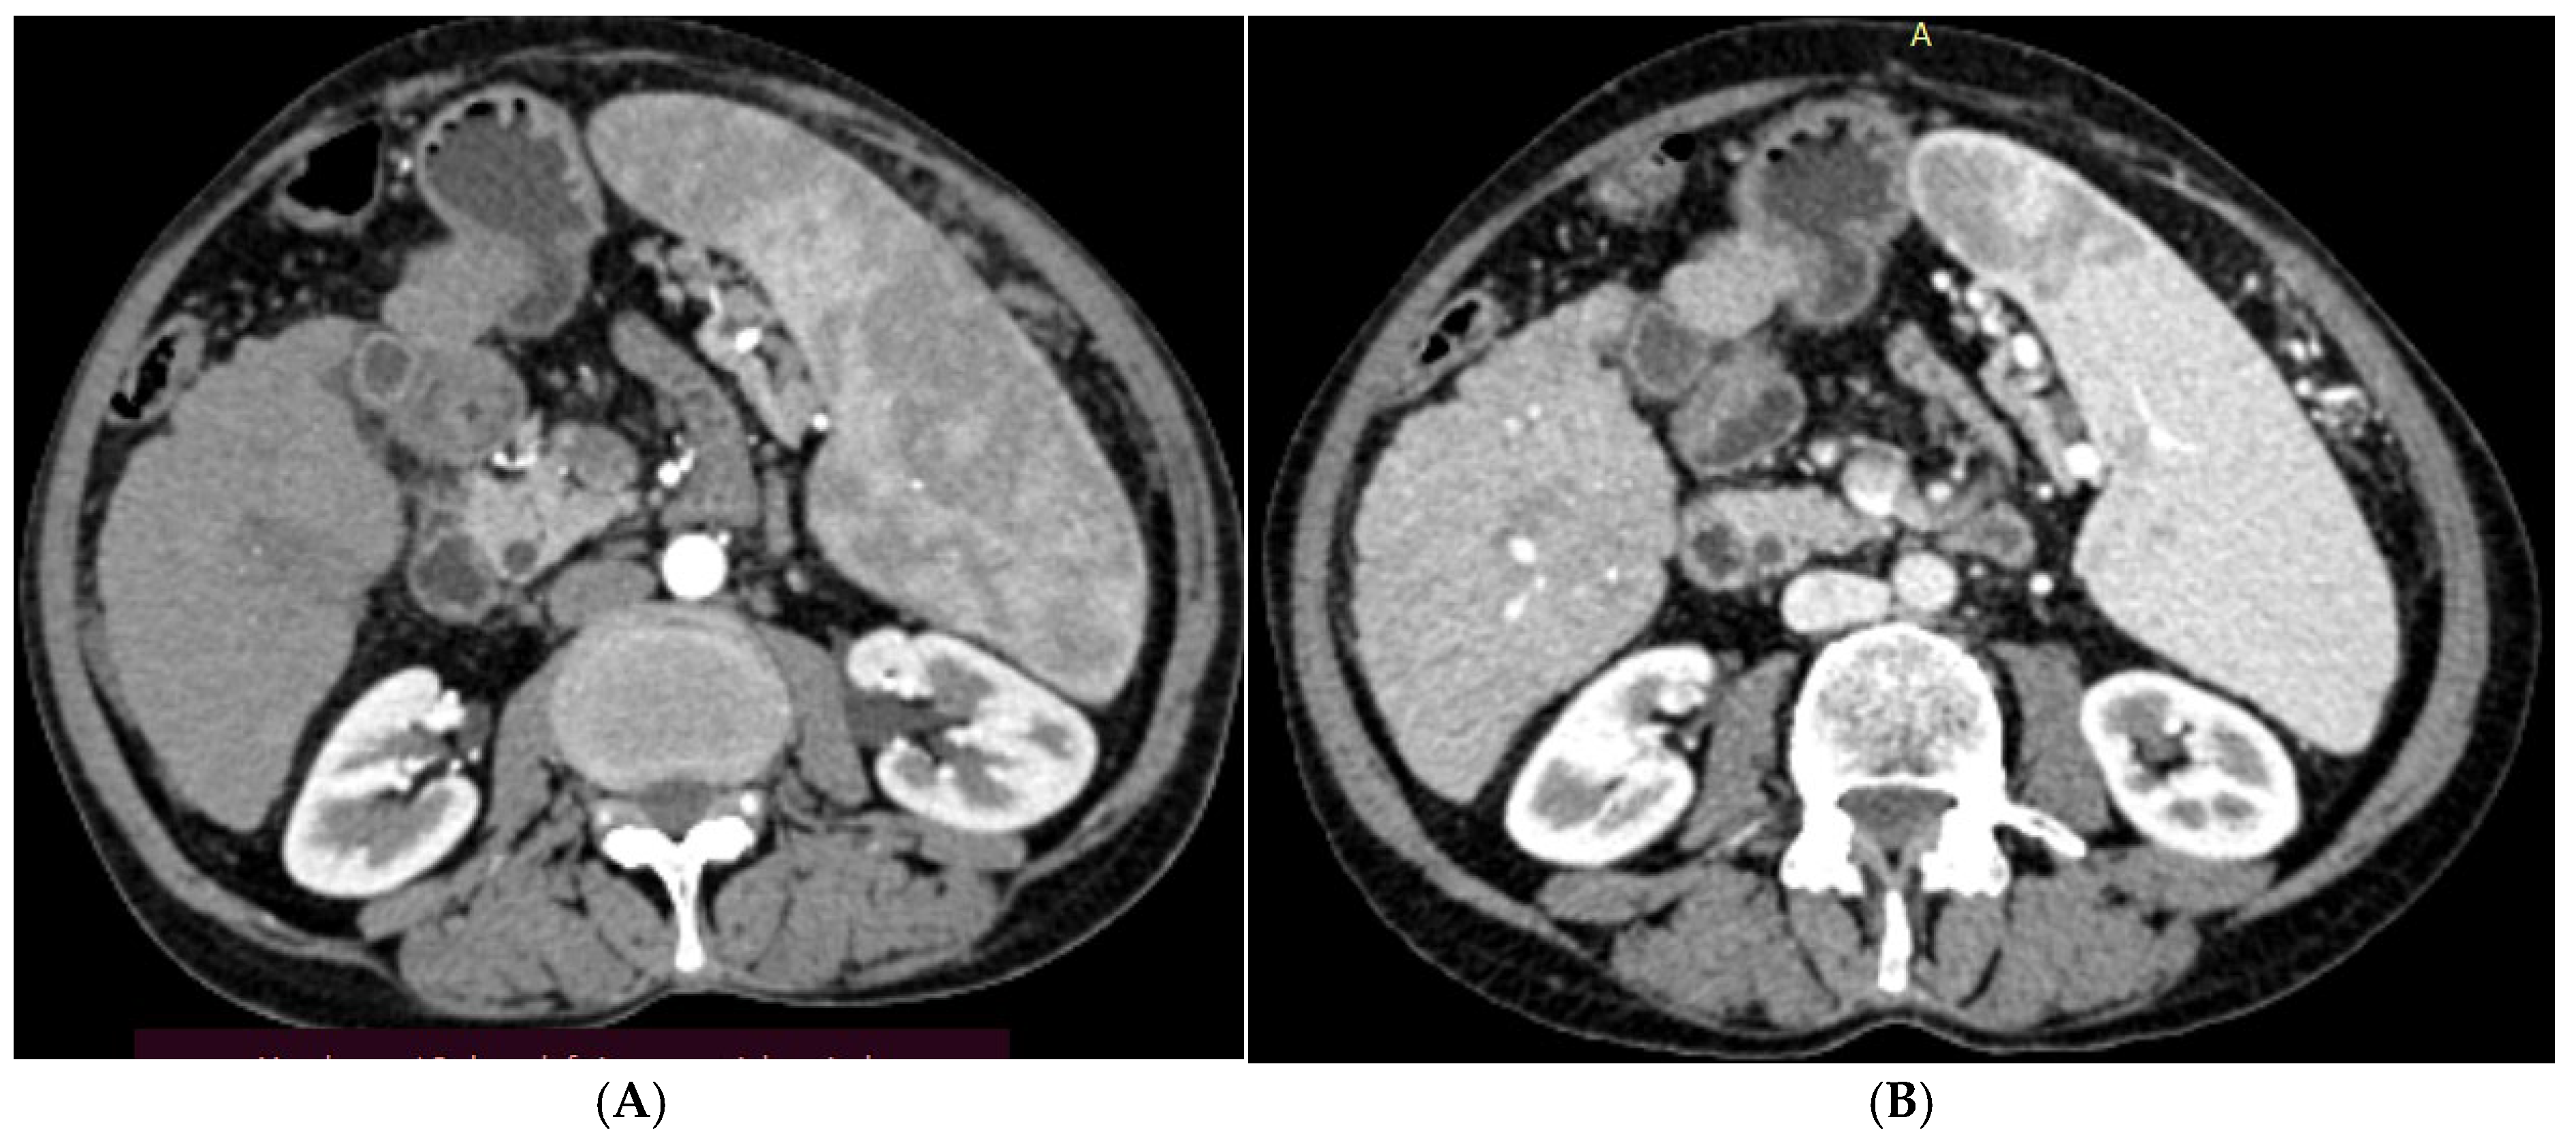

2.2.2. Procedures